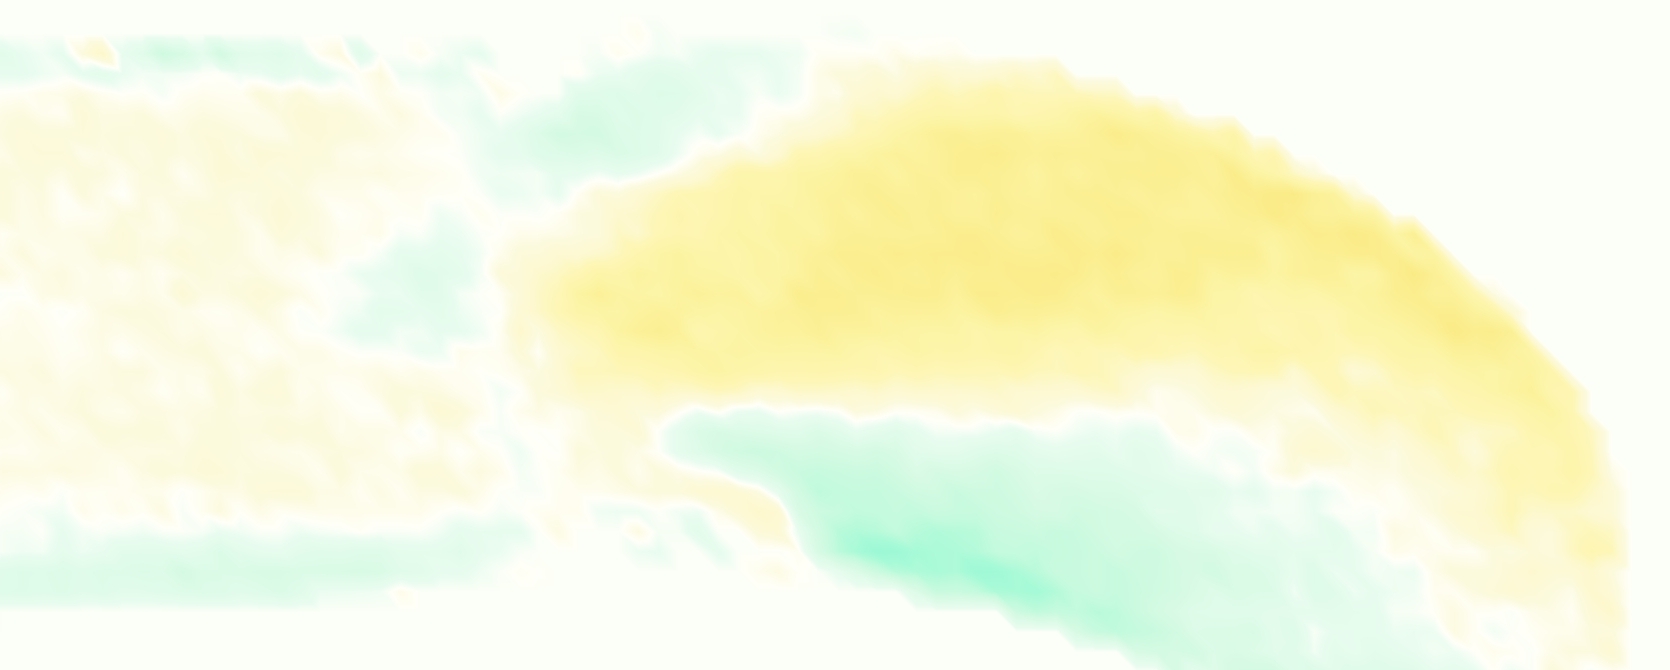

The emergent hemodynamics showed excellent qualitative agreement with experiments. Slice views of the axial component of fluid velocity ( component) in the sagittal plane that cuts through the center of the vessel, parallel to the flow direction, are shown in Figure 5. The flow in both the simulation and the experiment began to accelerate at the same time, with a jet forming through the open valve leaflets. The velocity, angle, and shape of the jet agreed well between the two cases during systole. The simulation captured the slight upward angle of the jet, which was not fully centered in the vessel. It also matched the location where the jet impacts the wall and the slower speed of the jet as it turns with the MPA downstream. As the flow decelerated, the fluid along the interior curve of the vessel reversed first while forward flow persisted where the jet was strongest, as seen in both the simulation and experimental results.

In both the experiment and the simulation, a separation region of reverse flow developed along the interior curve of the vessel under the core jet through the valve. The reverse flow began to develop at the same time in the cardiac cycle and grows throughout systole. The simulation lacked reversed flow in the entire region where reversed flow was present in the experiment, but this region developed some flow separation and had much slower flow than elsewhere in the vessel. Thus, the simulation captured that this is a distinct region from the core jet through the valve opening. There was a smaller amount of slower and slightly reversed flow along the outer curve of the vessel, close to the valve annulus and scaffold support. This region was well-matched between the experiment and the simulation.